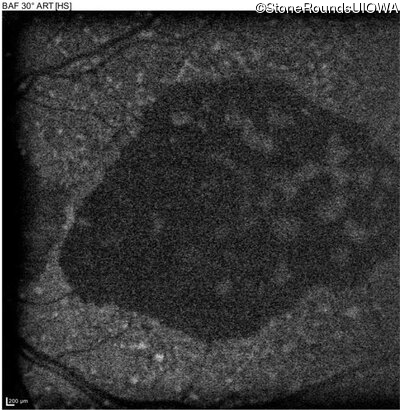

AR Stargardt Disease (IIA)

Age at visit: 59 years

This 59 year old man has noticed some blank spots near the center of his vision over the last 2 years.

AR Stargardt Disease ABCA4 Leu2027Phe CTC>TTC IVS30+1321 A>G AR